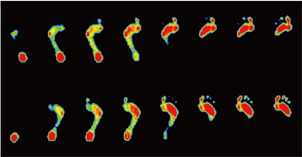

フレーム分布

歩行時の接地状態を0.06秒毎のコマ送りにしたデータです。左右のフレーム数の違いから被験者へ荷重時間の差を視覚的に説明する事が出来ます。

3D表示

歩行周期を時間観察します。

同時期の左右の足を比較対照します。